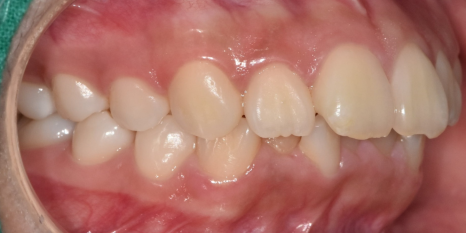

교합 상태, 치아 배열 상태를 확인하기 위해

5분할 포토라 불리는 구강 내 사진을 찍고

뽄도 뜹니다.

교정 모델을 만들기도 하며

이 과정에서 구강 스캐너가 동원되기도 합니다.

앞으로 교정을 통해 치아가 어떻게 움직일지 예측합니다.